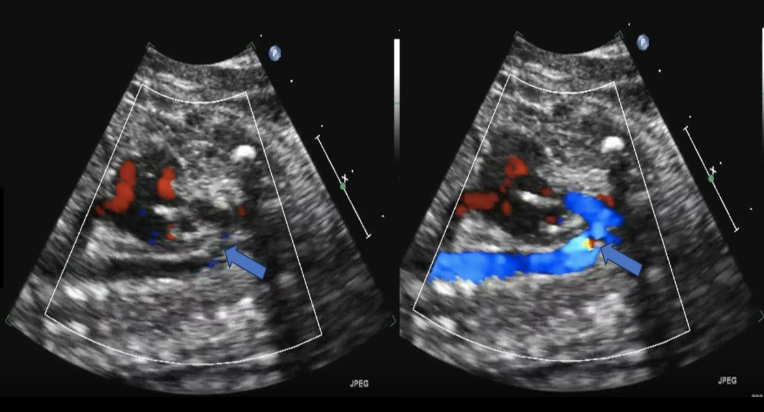

while performing an anatomy scan on a 22w fetus, you are unable to obtain a cross-sectional image of the umbilical cord to show the number of umbilical arteries.

.

what is an alternative method to evaluate the arterial anatomy of the cord

a) obtain a cross-section view of the umbilical cord insertion at the placenta + apply color doppler

b) obtain a transverse view of the fetal abd at the level of the kidneys + apply color doppler

c) obtain a transverse view of the fetal pelvis at the level of the bladder + apply color doppler

d) obtain a midline sagittal view of the fetus that includes the fetal bladder + apply color doppler